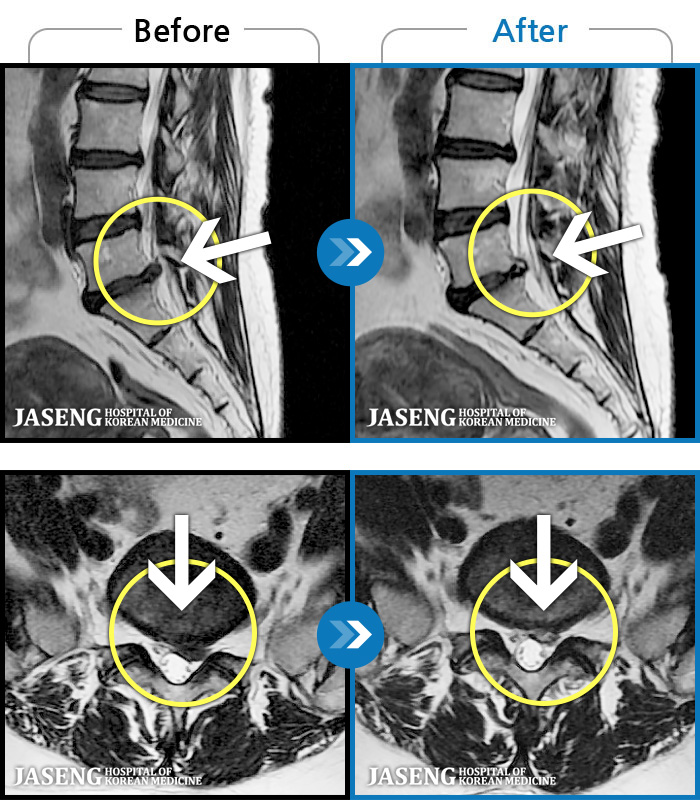

1,237 MRI ũ ʸ Ȯϼ.

MRI ġ

㸮 ϻ .